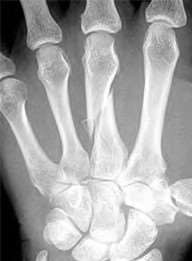

volar tenderness along the flexor sheath

Patients commonly present 24 to 48 hours after onset of symptoms. The standard of care is “urgent surgical drainage” to avoid tendon scarring or necrosis with subsequent impairment of finger function followed by intravenous antibiotic administration.

According to Hand Surgery Update 3, open sheath irrigation has been replaced

largely by closed sheath irrigation. These authors cite a retrospective study that showed no statistical difference in resolution of infection using open sheath irrigation or closed sheath irrigation, however, there was a trend towards more frequent complications and reoperations in the open drainage group.

Lille et al reviewed the records of 75 patients with pyogenic flexor tenosynovitis and found that there was no difference in outcomes between those who received intraoperative irrigation only versus those receiving intraoperative irrigation and continuous postoperative irrigation.